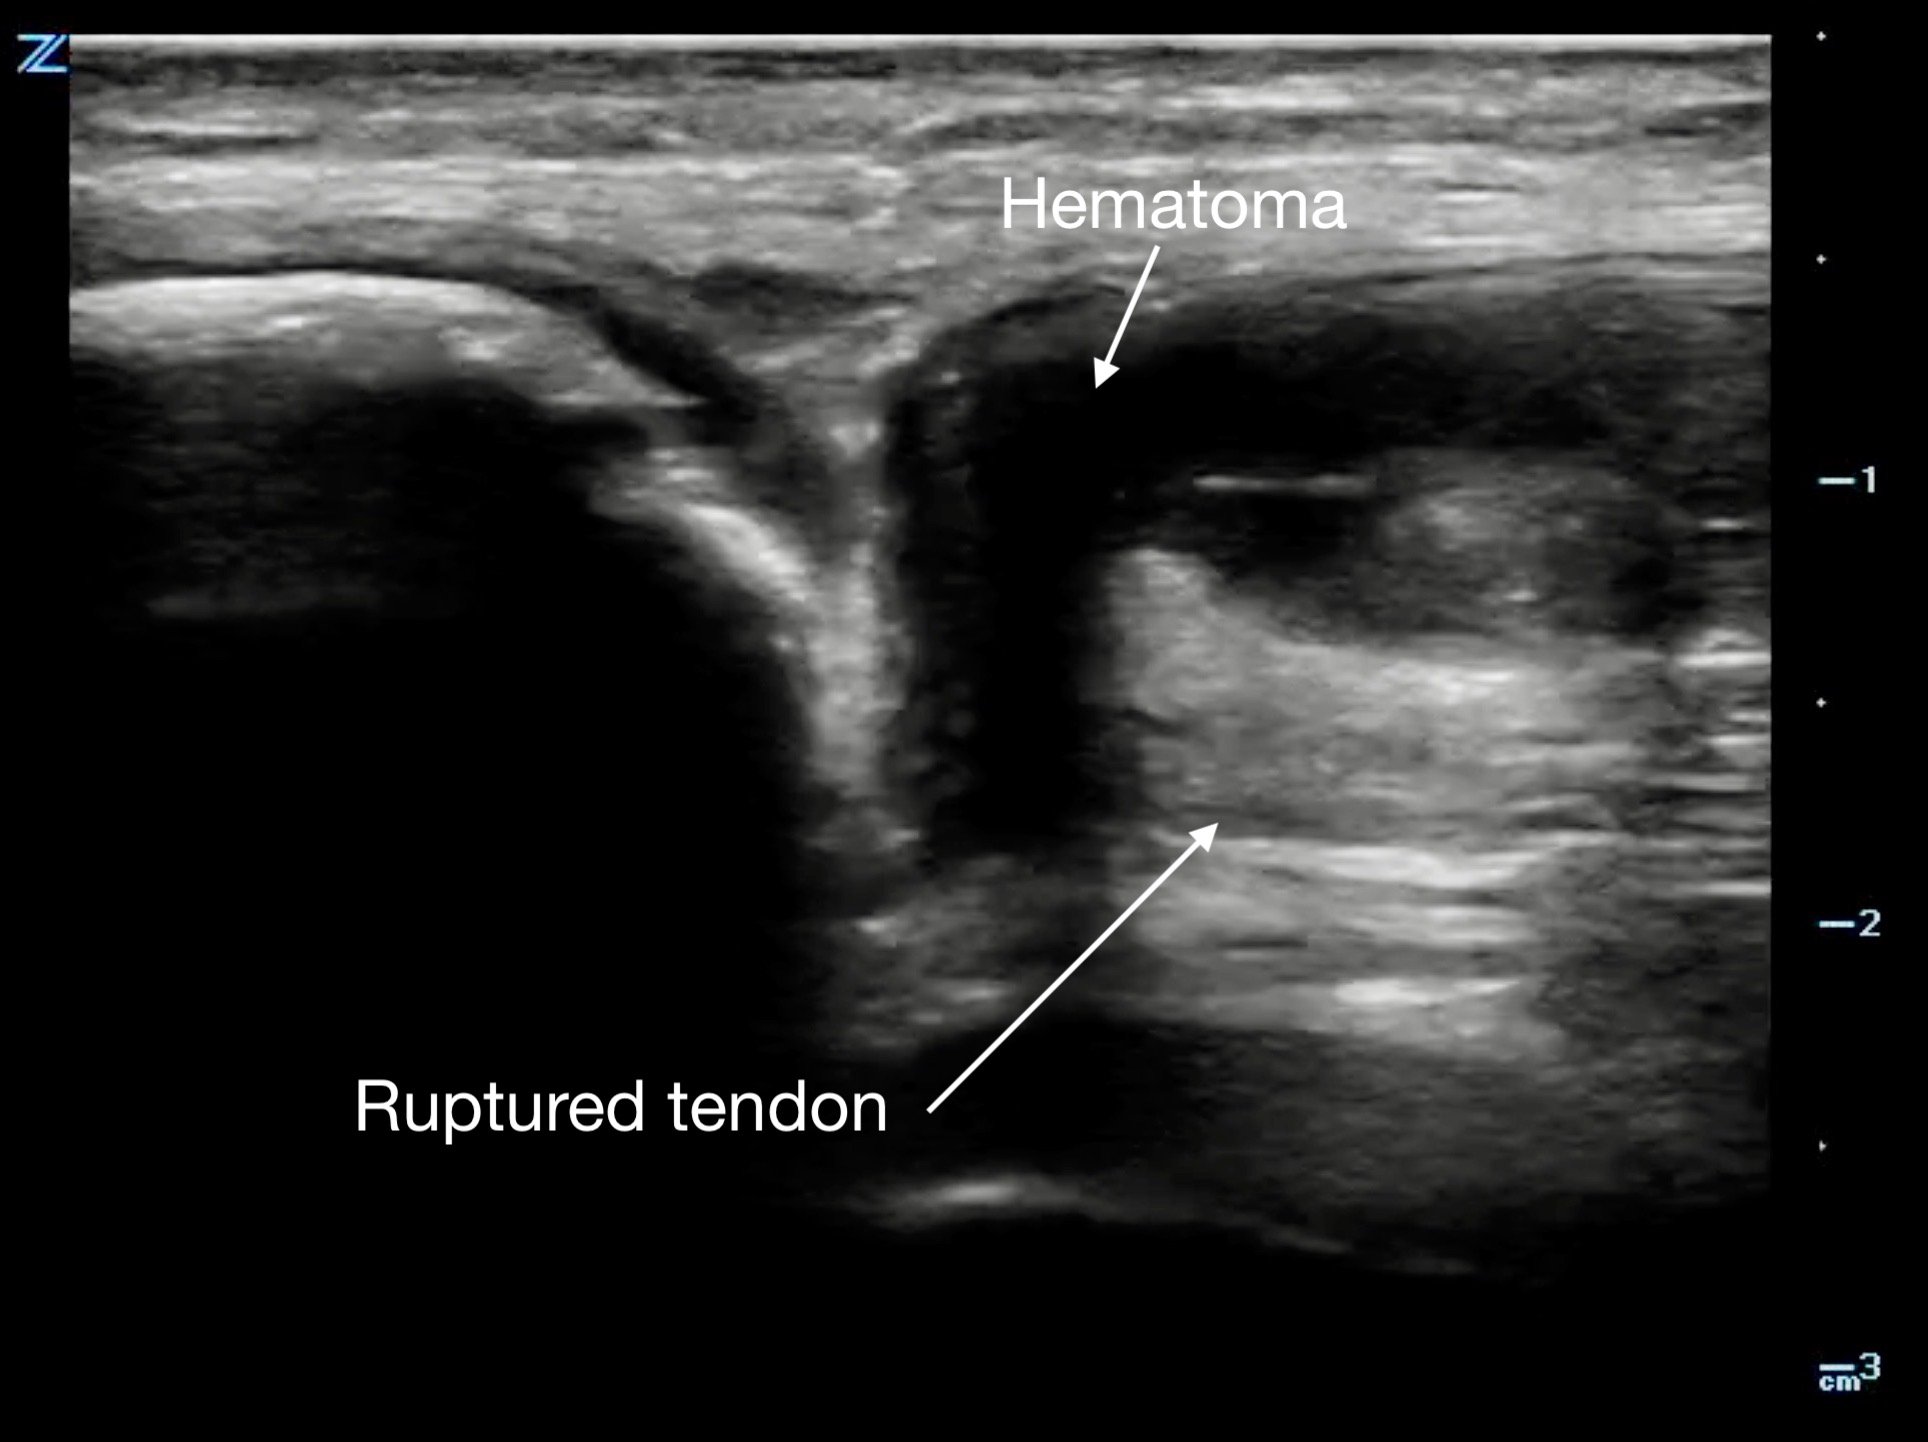

Tendon ruptures appear as areas of hypoechogenicity from edema/hematoma, and adjacent bunched up, retracted tendon fibers. For complete tears, the portion of the tendon near the injury will lose its rigid, straight appearance and instead appear irregular and have a large gap between the torn end and its insertion point. Partial tears are more subtle and will sometimes only have a small, cone-shaped hypoechoic focus. The key with tendon exams is to view them dynamically, having the patient flex and extend the injured joint (if possible).

Figure 13b.

a different patient with a complete rupture at the proximal insertion of the patellar tendon. The patella is on the left side of the image, and note the hematoma that wraps around the ruptured end of the tendo